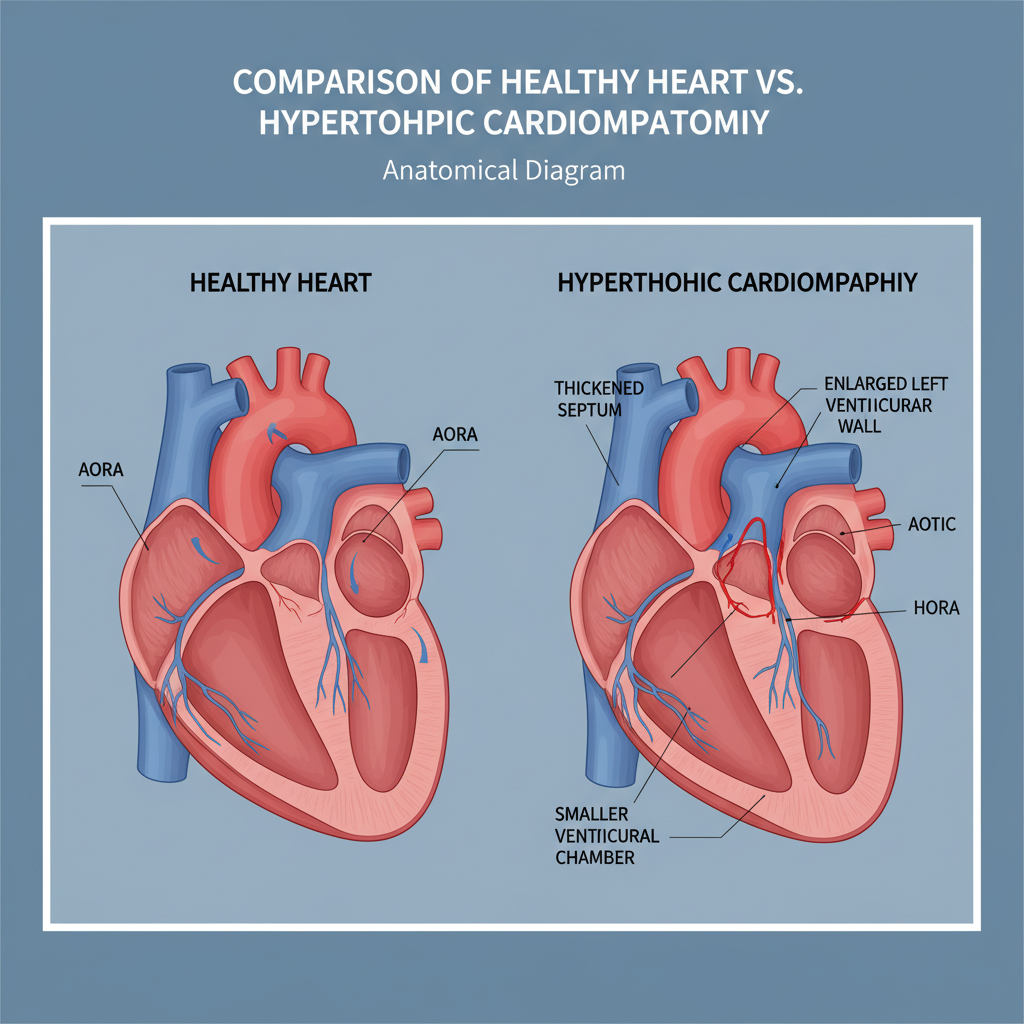

Bệnh cơ tim phì đại là một tình trạng bệnh lý tiềm ẩn có thể gây ra nhiều tương tác nghiêm trọng với sức khỏe. Nhận biết sớm và điều trị đúng cách là rất quan trọng để bảo vệ trái tim của bạn. Hãy...

Bệnh cơ tim phì đại là một tình trạng bệnh lý tiềm ẩn có thể gây ra nhiều tương tác nghiêm trọng với sức khỏe. Nhận biết sớm và điều trị đúng cách là rất quan trọng để bảo vệ trái tim của bạn. Hãy...